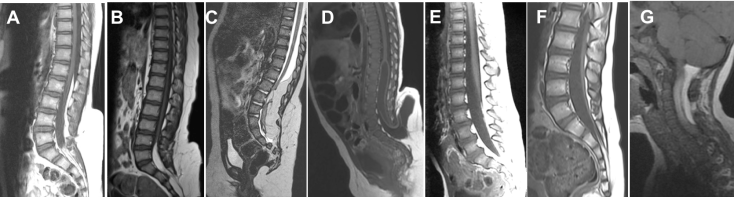

on distingue :

- le lipome terminal : la moelle se termine par le lipome dans le fond du cul-de-sac sacré

- le lipome postérieur : le lipome adhère à la face postérieure de la moelle, la moelle et/ou les racines se poursuivent en dessous de la limite inférieure du lipome

- le lipome transitionnel : il combine les deux précédents, des racines nerveuses sortent du lipome

- la myélolipocystocèle terminale : la moelle se termine par un lipome qui adhère au fond d’une poche méningée sous cutanée basse

- le film lipomateux : le film est épaissi, chargé de graisse, souvent court et tendu

la classification de ces différents types de lipomes est malgré tout arbitraire et il existe en fait un bon nombre de cas intermédiaire, il s’agit plus d’un continuum que d’entités bien individualisées.